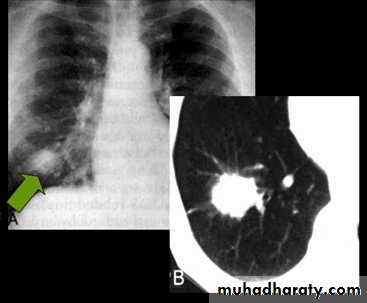

Chest X-ray shows radio-opaque (white) nodular lesion in the right mid-lung field.

Dx:x chicken pox , Histoplasmosis (calcified granuloma).